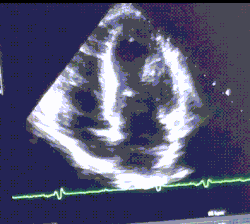

Athlete's heart is usually an incidental finding during a routine screening or during tests for other medical issues. An enlarged heart can be seen at echocardiography or sometimes on a chest X-ray. Similarities at presentation between athlete's heart and clinically relevant cardiac problems may prompt electrocardiography (ECG) and exercise cardiac stress tests. The ECG can detect sinus bradycardia, a resting heart rate of fewer than 60 beats per minute. This is often accompanied by sinus arrhythmia. The pulse of a person with athlete's heart can sometimes be irregular while at rest, but usually returns to normal after exercise begins.[12][13][14]

- Echocardiography – differentiation between physiological and pathological increases of the heart's size is possible, especially by estimating the mass of the wall (not over 130 g/m2) and its end diastolic diameter (not much less 60 mm) of the left ventricle.[9][23]